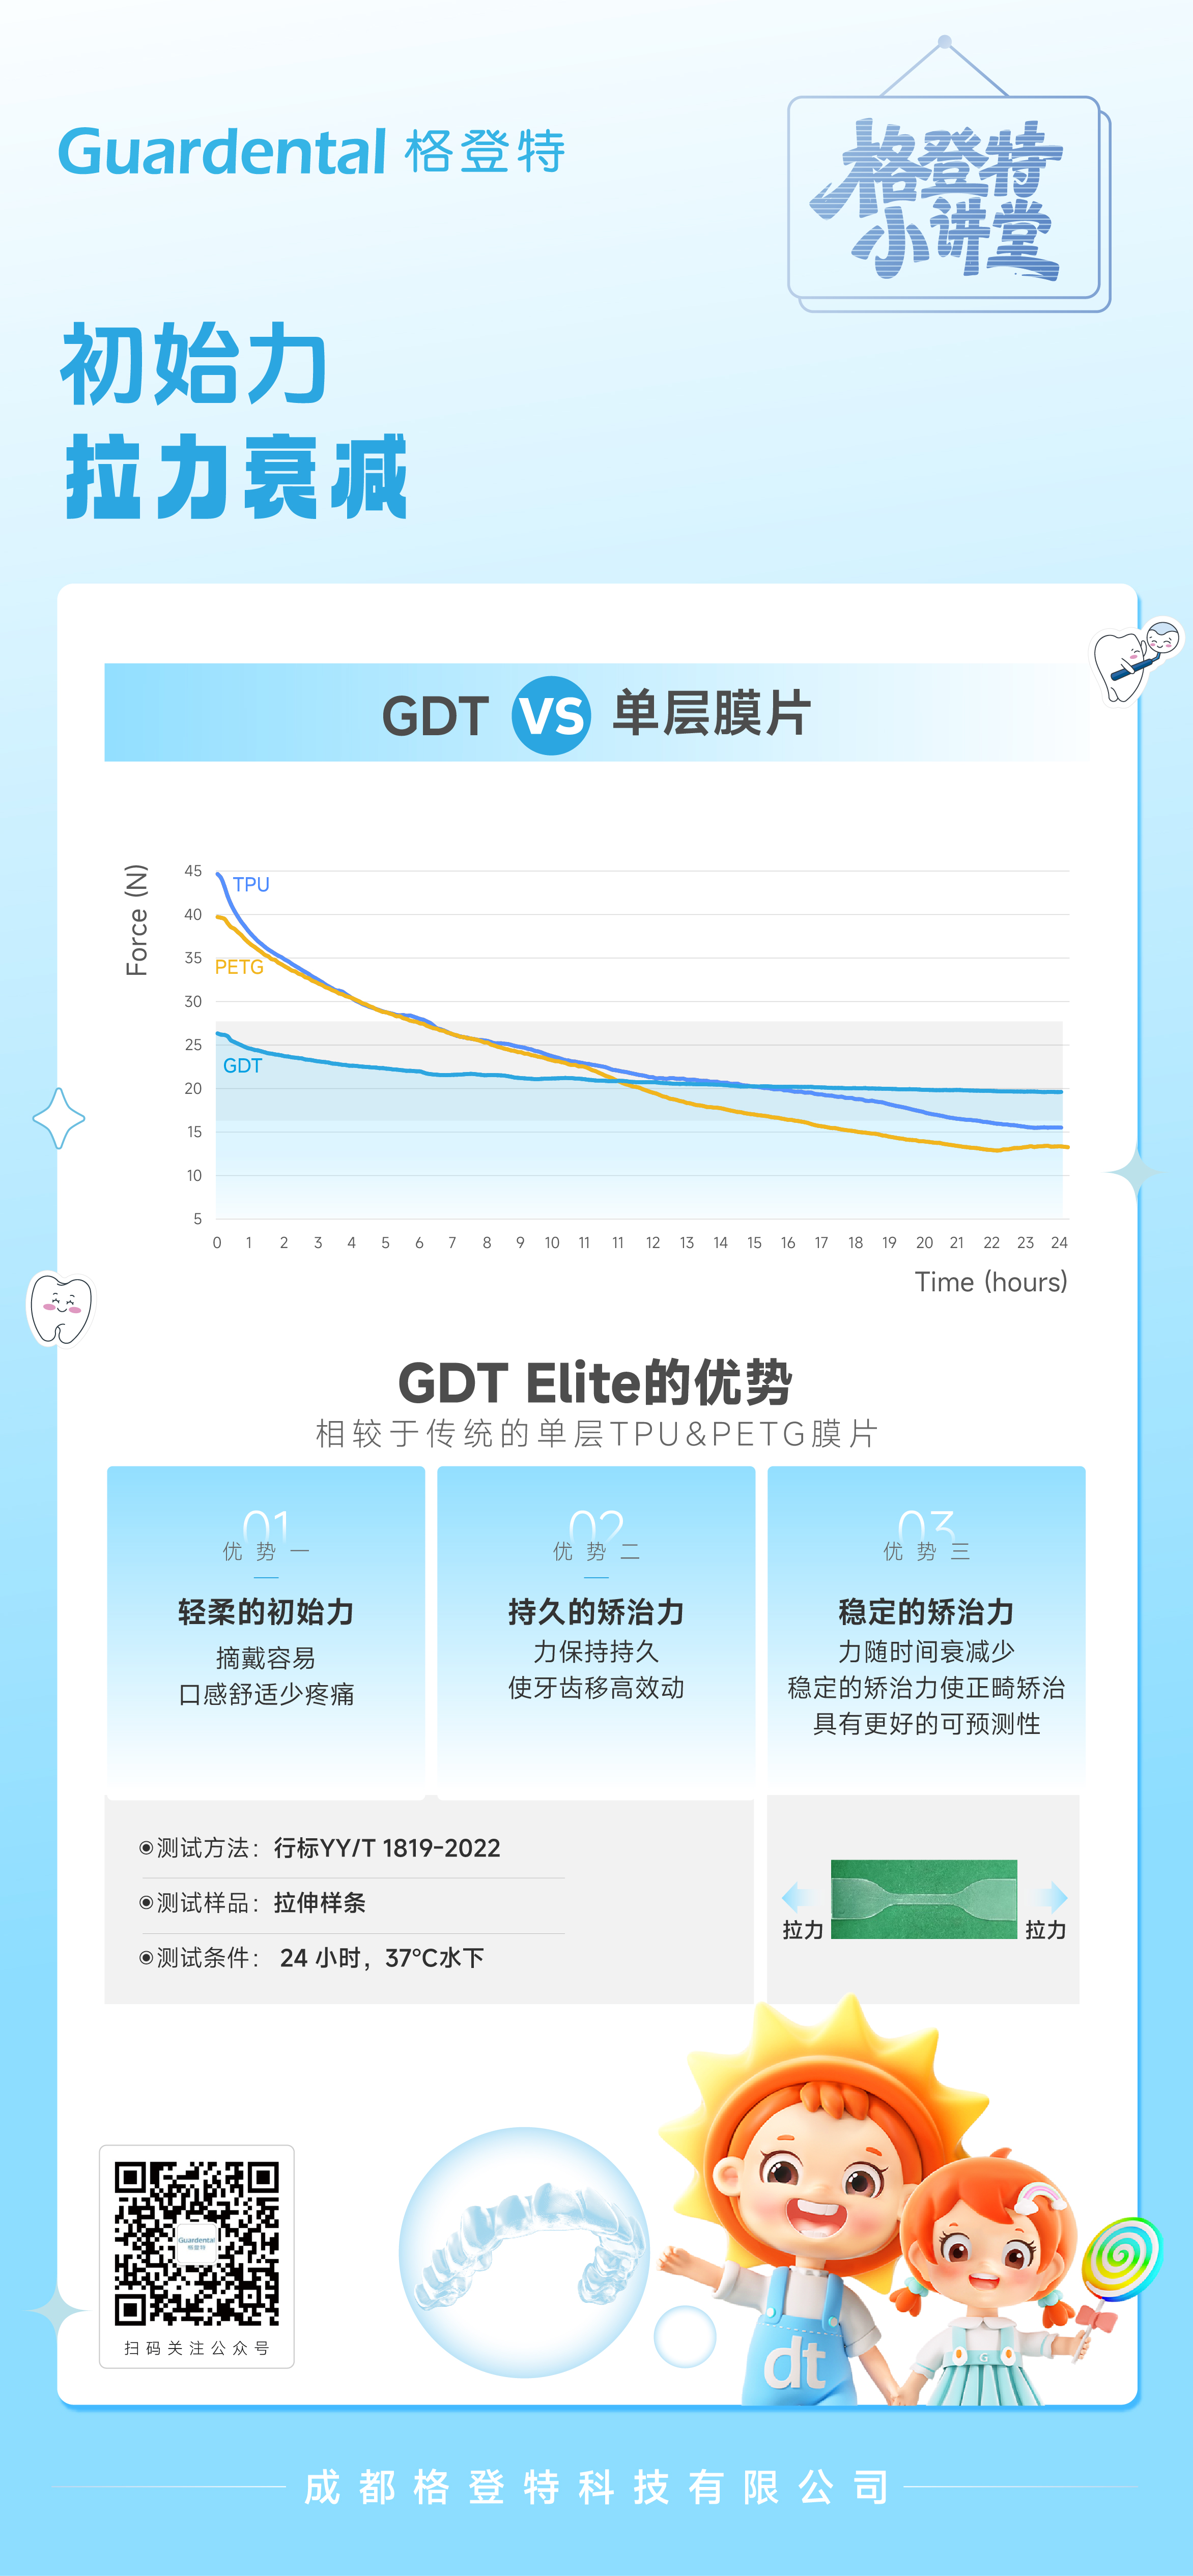

产品名称为“定制式透明矫治器”,由成都格登特科技有限公司生产,医疗器械注册证号为“川械注准20242170269”。产品的禁忌内容及注意事项等详细信息,请务必查阅产品说明书。